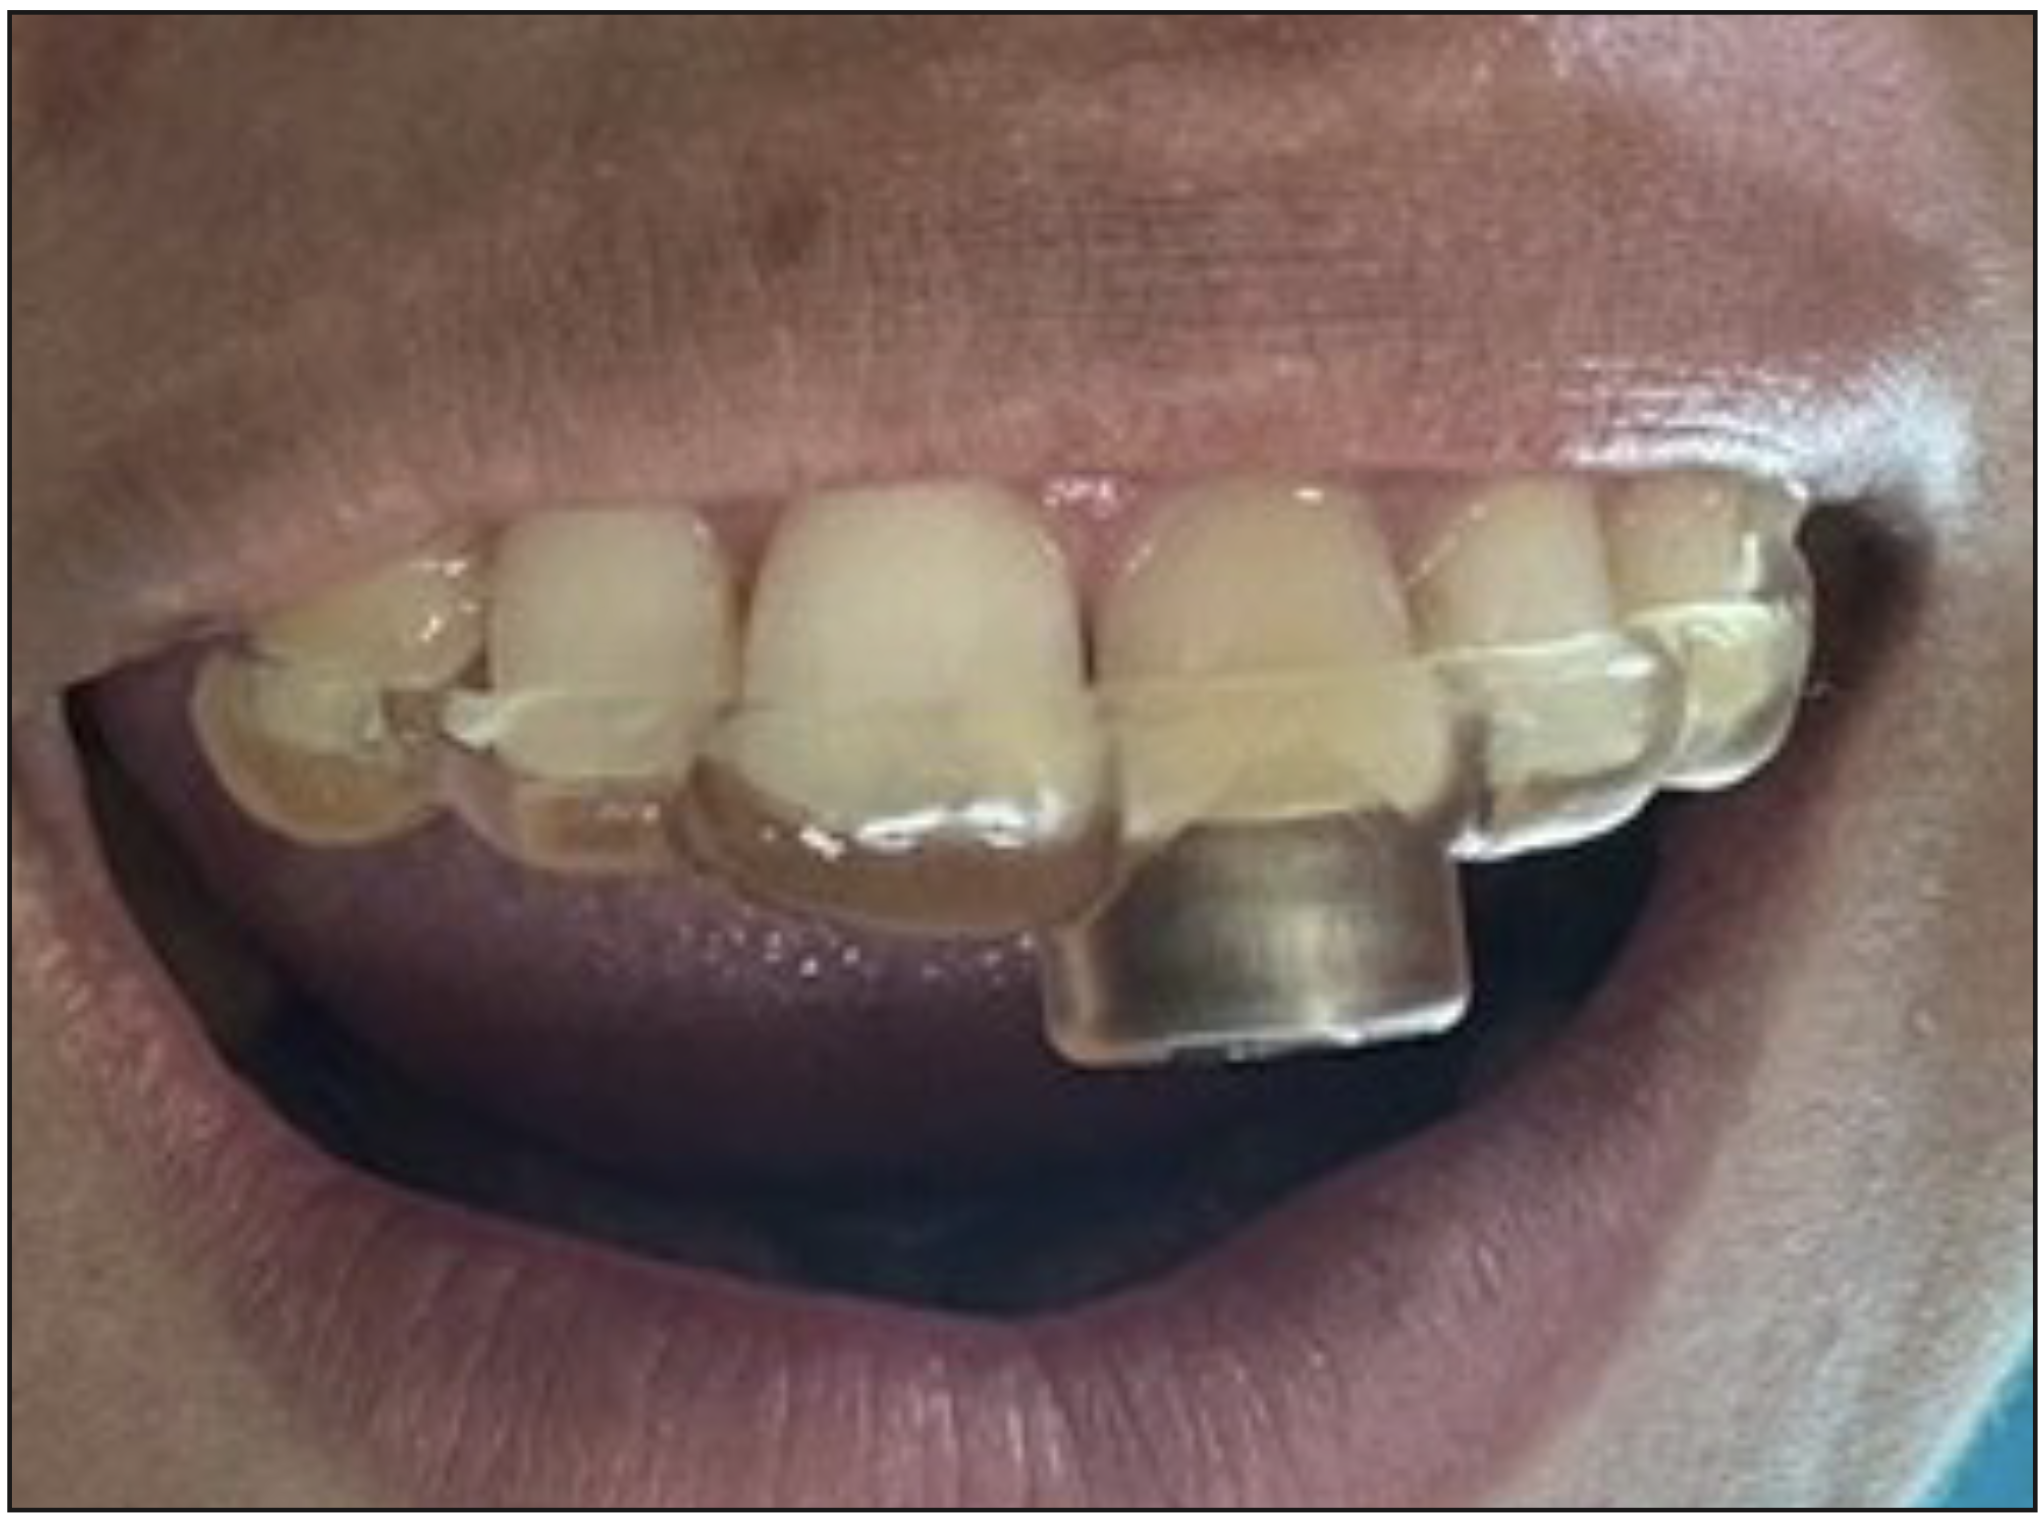

Dada la complejidad del caso, se indico realizar una endodoncia guiada, por lo cual se realizó una tomografía computarizada de haz cónico (CBCT), y escaneo intraoral, para la confección de una guía estática (Figura 2). Posterior a la etapa de laboratorio, se realiza la prueba de la guía estática, para el chequeo de la estabilidad y del eje de acceso planificado.

Figura 3. Prueba de guía estática para realizar el acceso guiado.